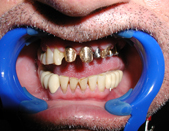

The term ‘Dental Implants’ refers to the surgical placement of artificial roots which help replace missing or badly damaged teeth. Other methods to replace missing teeth include dentures or bridges. The advantages of Implant tooth restoration is that it presents a more permanent solution.

Dentures are removable and tend to stay loose while they are worn. Full Dentures also affect the wearer’s diet. The ability to bite down can decrease by approx. 90%. Partial Dentures rely on adjacent teeth for help when biting. The long term affect of partial dentures leads to the loosening of the remaining teeth in the mouth. Dentures are recommended as a temporary resort or a last resort for patients that can not have implants due to medical complications, or lack of supporting bone.

Dental Bridges refers to the use of the adjacent teeth on either side of an empty space, to fill out the space and restore the function (or esthetics) of a missing tooth. Up until the invention of Implants, this procedure was considered the best way to restore the space created by a missing tooth. The two adjacent teeth are cut down and a cast metal and porcelain ‘suspension bridge’ is made to allow for the missing area to be filled out.

The advent of Dental Implants removed the need to cut down adjacent teeth to restore a missing tooth. In most cases an implant can fill out the missing space and restore the esthetic look of the area with no collateral damage. The adjacent teeth can live happily ever after, instead of needing to support a missing tooth, they now can enjoy the support of the adjacent implant crown.